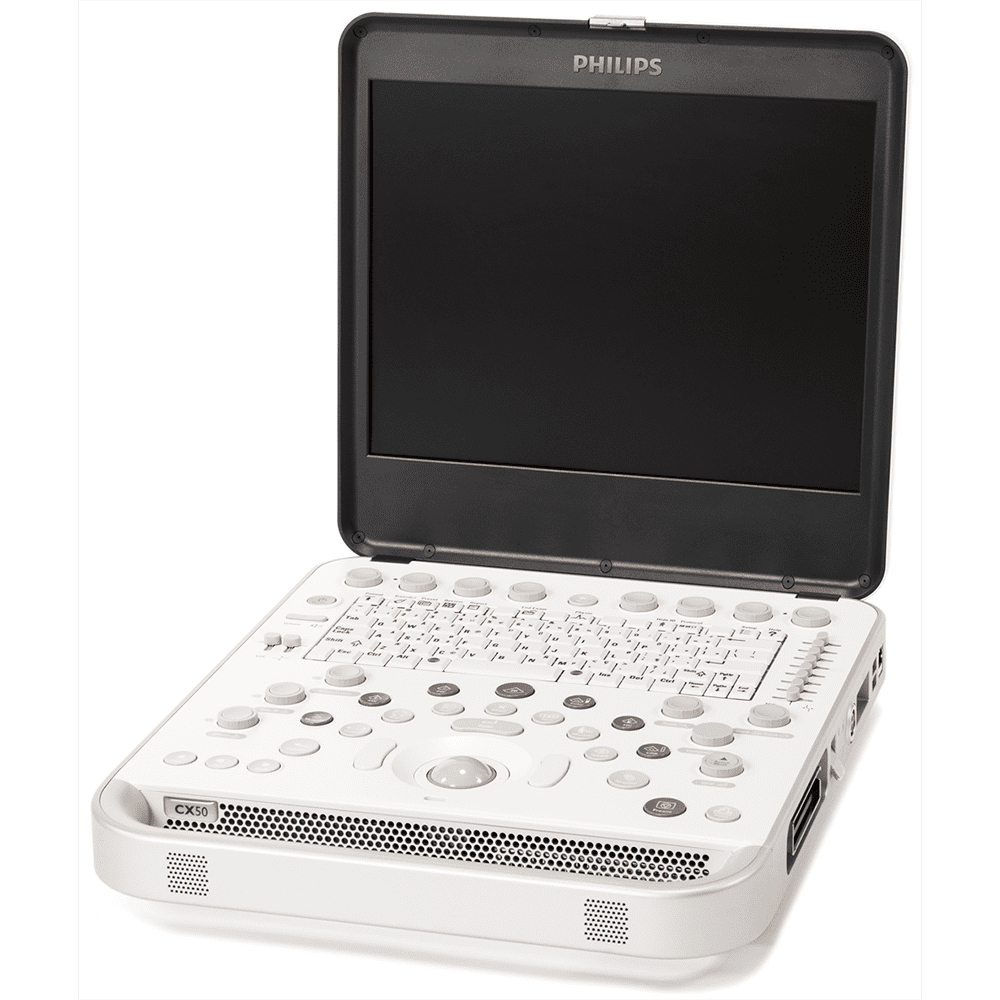

УЗИ система Philips CX50

Портативная многофункциональная УЗ-система Philips CX50 предназначена для общих исследований и сочетает в себе современные технологии, которые выводят ее на новый уровень качества изображения. Система соответствует требованиям к отделениям интенсивной терапии и обладает производительностью стационарных систем.

Компактная ультразвуковая система для любых условий работы

Филипс CX50 оснащена монитором с высоким разрешением, обеспечивающим оптимальный просмотр изображений в сложных условиях вне процедурной, а быстрое включение аппарата позволяет оперативно начинать исследования. Функции проводной и беспроводной передачи данных по протоколу DICOM позволяют связываться с архивом PACS в любых ситуациях. Можно также экспортировать данные на диск DVD или USB-носитель с помощью встроенной программы просмотра DICOM-изображений.

- 15-дюймовый дисплей высокого разрешения с широким углом обзора;

- Оттенки серого: 256 уровней (8 бит) в режимах 2D, допплера и М-режиме;

- Количество портов для датчиков: 1;

- Клавиши быстрого доступа и активный режим;

- Алфавитно-цифровая клавиатура QWERTY типа Лэптоп;

- Включает адаптер переменного тока, шнур электропитания и аккумуляторный блок системы;

- 2 USB-порта;

- Жесткий диск: 80 Гб;

- Встроенный дисковод: CD / DVD RW;

- 1 порт для датчика (разъем для непрерывно-волновых датчиков);

- 8 уровней TGC и 2 уровня LGC;

- Вес: 6,17 кг;

- Размеры (Ш×В×Г): 413*76*356 мм;

- Аналого-цифровое преобразование с высоким разрешением;

- Класс: экспертный;

- Тип: портативный.